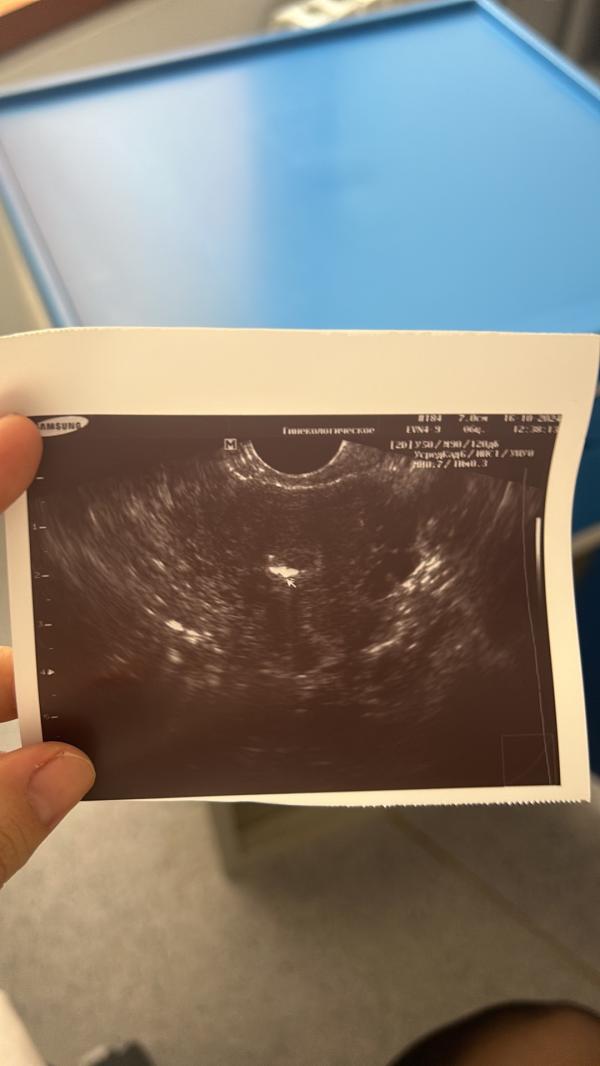

16 окт 24 сделали перенос моей булочки❤️

Вообще на самом деле такая интересная история с дочей: это был мой второй протокол ЭКО, в день моего рождения! я пришла на перенос и до того как меня забрали я зашла к врачу он сказал что до 5 дня дожил только 1 эмбриончик. Я конечно немного расстроилась что больше не получилось. Но когда я уже лежала на кресле - в окошке эмбриолог сказал « я вас обрадую, еще один эмбрион дал развитие» ! Я тогда подумала , действительно хвала Аллаху, подарок на Др. И вот перенос который был в день рождение оказался неудачным из-за тромбофилии. Мы с РТ нашли причину неудач, прошли терапию и пошли в третий протокол. А мой второй эмбриончик,который был моим подарком Всевышнего был перенесен и сейчас сопит рядышком❤️

Ой как прекрасно, поздравляю вас ! Пусть ваша малышка растет Вам на радость 🌸 понимаю ваши чувства благодарности , дай Аллах испытать эти чувства - я прям жду апрель чтобы взять малыша на руки - вчера посмотрев на узи будто уже чуть чуть и он будет рядом было ощущение.. это так прекрасно 🌟